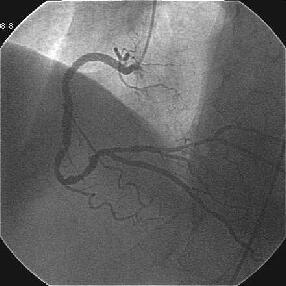

Crush���KBT.

|

|

|